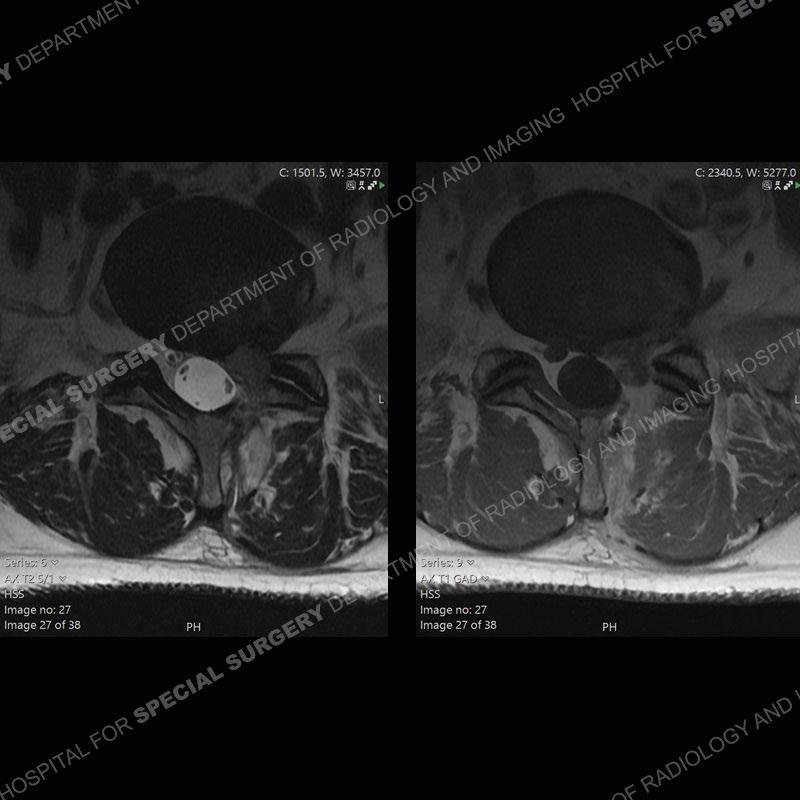

Post operative changes are seen on the left side at L5-S1 where there is near complete removal of the left sided L5 lamina, partial resection of the left L5-S1 facet joint, and resection of the left sided ligamentum flavum. In the anterolateral epidural space about the subarticular recess is a mass that demonstrates similar T1 and T2 signal characteristics to the adjacent degenerated disc. There is enhancement about the periphery of the mass, but the majority of this somewhat geographic or polyploid mass demonstrates no enhancement. The mass exerts prominent mass effect on the left S1 axillary sleeve/proximal nerve root. The left S1 nerve root shows enlargement and increased enhancement as compared to the contralateral right side.

Diagnosis: Recurrent Disc Herniation

Not as much of a diagnostic dilemma as some other cases but more so just a very nice example of what can be a difficult assessment at times. The evaluation of granulation tissue/scar/epidural fibrosis vs. disc herniation particularly in the earlier post operative period can be very difficult. Clues that can assist in identifying a disc herniation are a more geographic or polypoid nature to the mass, signal characteristics similar to the adjacent degenerated disc, mass effect upon the thecal sac/adjacent neural structures, and a typical enhancement pattern. As the disc material is avascular, as long as imaging is performed in a relatively rapid fashion after contrast administration (within 20-30 minutes), the granulation tissue around the disc will enhance but the disc material itself will not. If there is a marked delay between contrast administration and imaging, there may be diffusion of contrast into the disc making the assessment very difficult. The marked utility of contrast to help delineate disc vs. scar has led to our institution employing contrast fairly uniformly within the first two years following surgery.